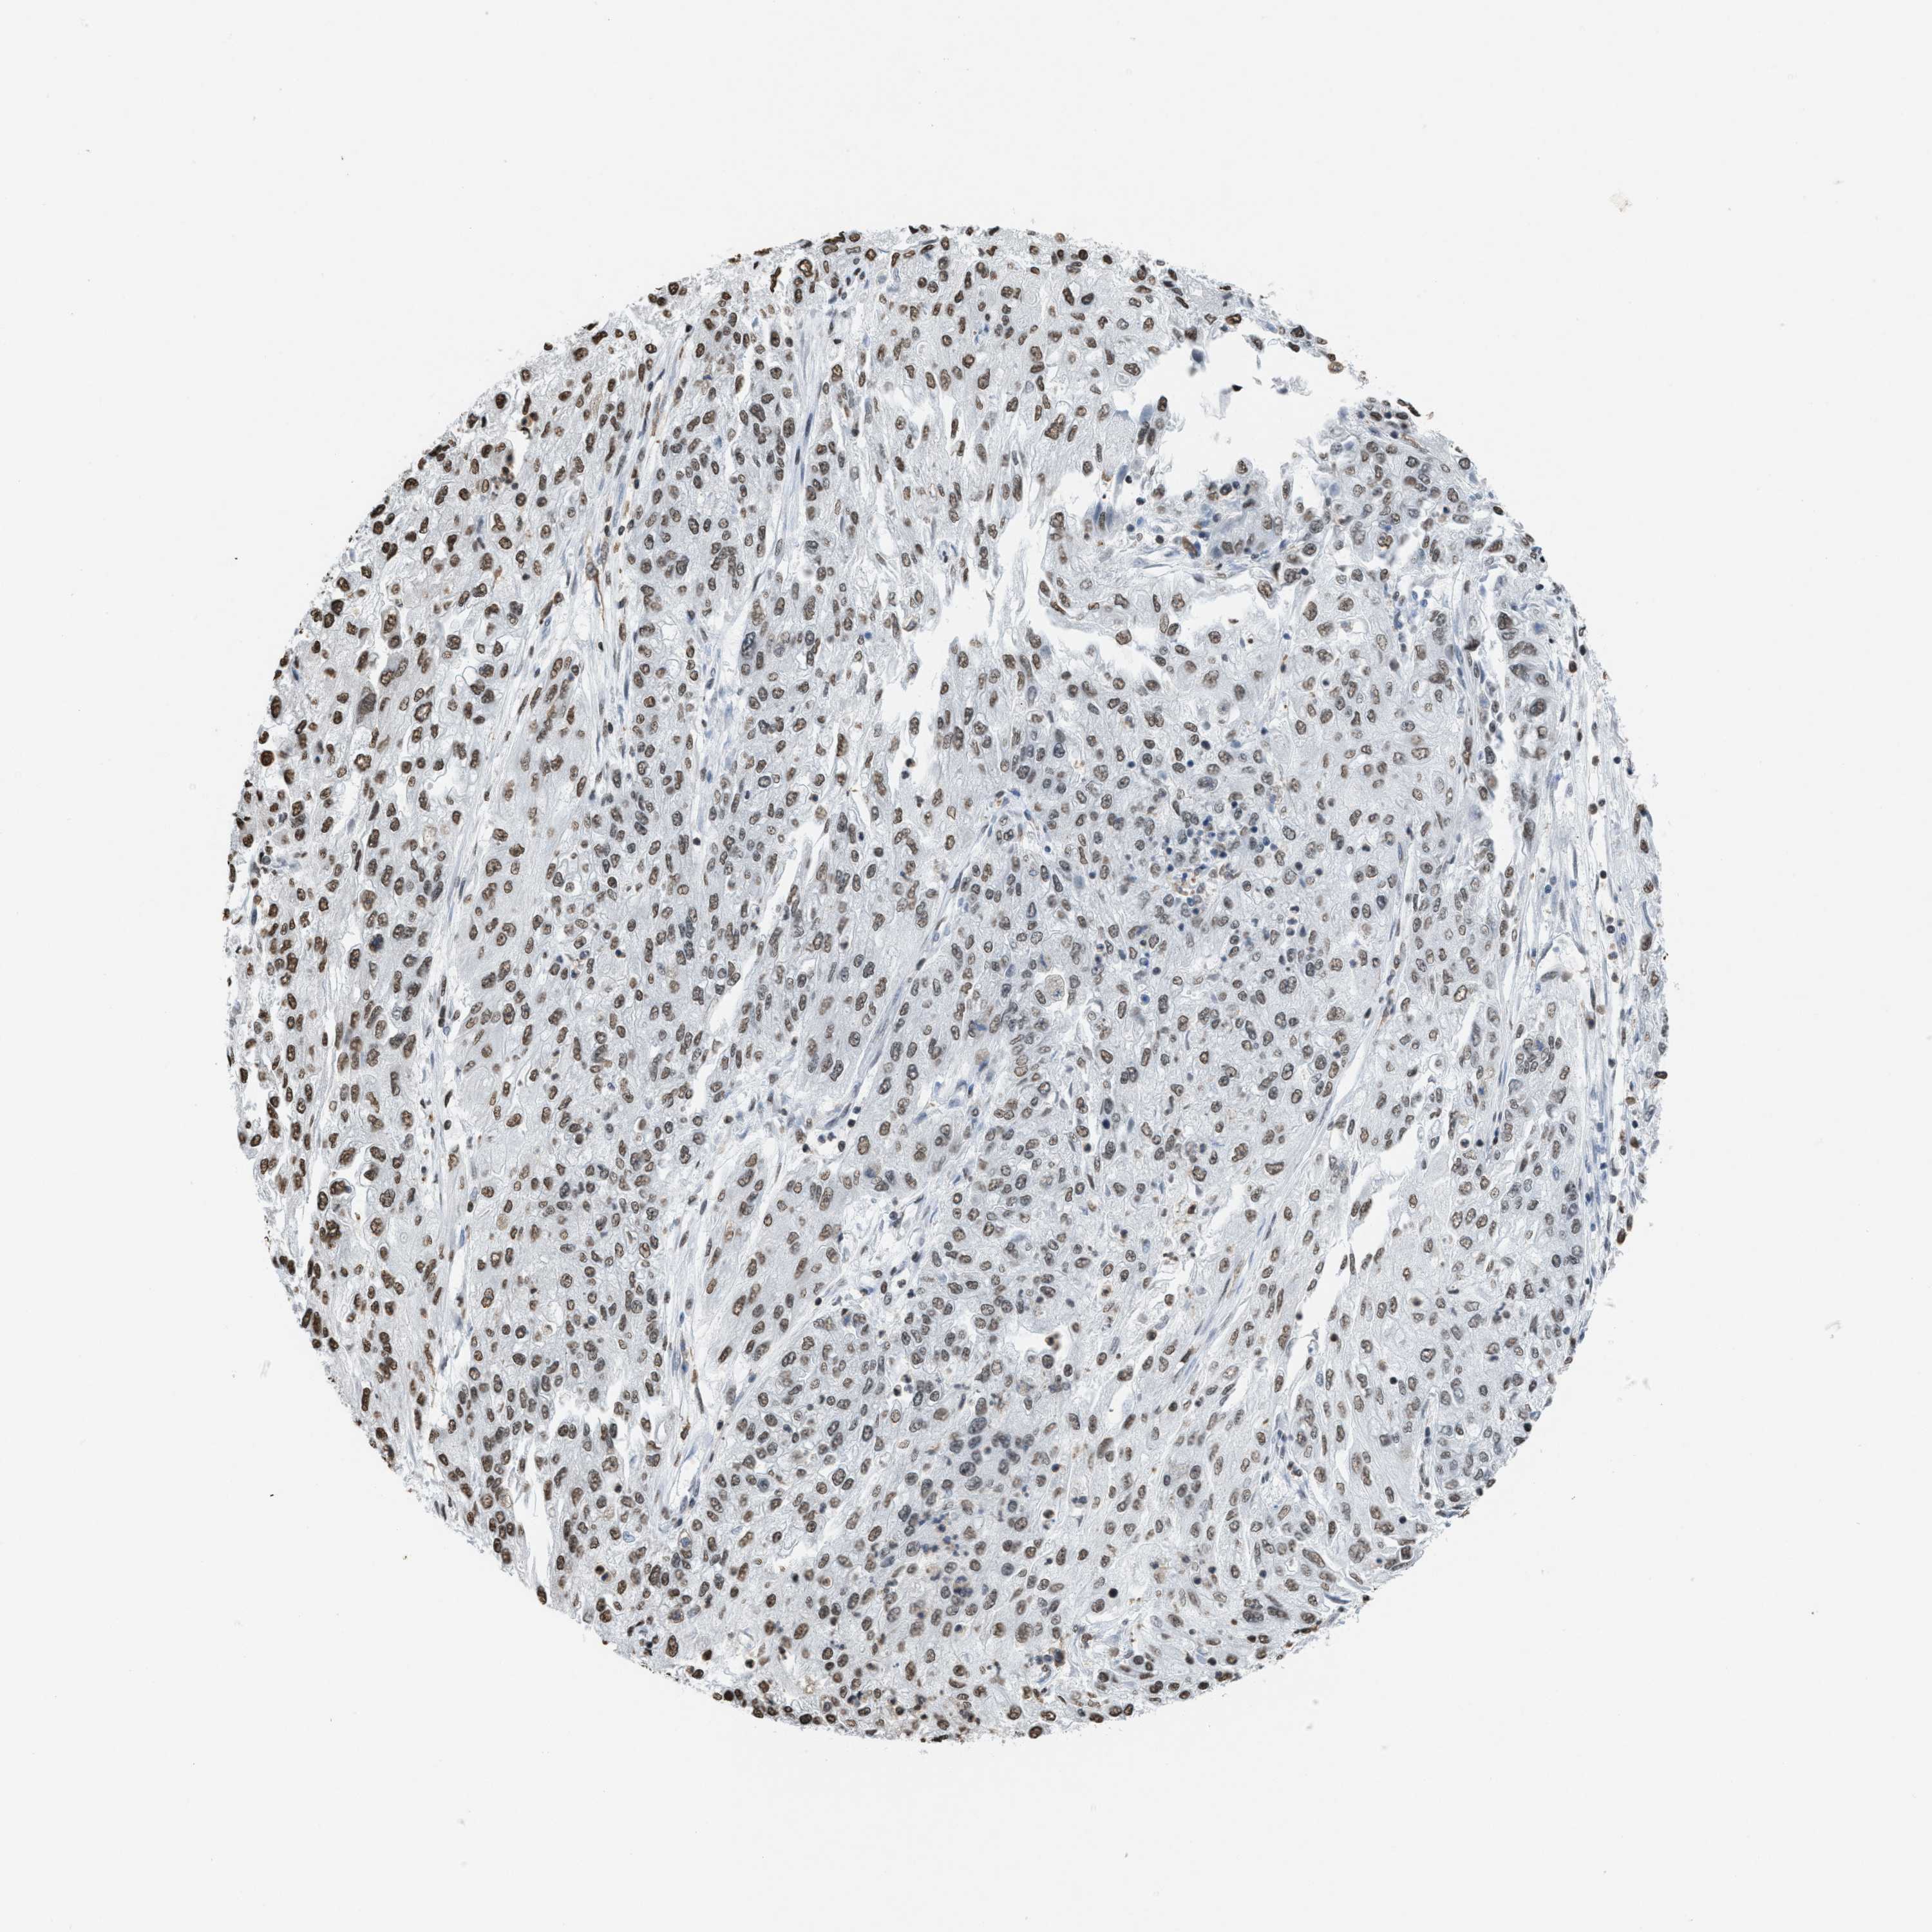

ENDOMETRIAL CANCER - Protein expressioni

A mouse-over function shows sample information and annotation data. Click on an image to view it in a full screen mode. Samples can be filtered based on level of antibody staining by selecting one or several of the following categories: high, medium, low and not detected. The assay and annotation is described here.

Note that samples used for immunohistochemistry by the Human Protein Atlas do not correspond to samples in the TCGA dataset.

Antibody stainingi

Antibody staining in the annotated cell types in the current human tissue is reported as not detected, low, medium, or high, based on conventional immunohistochemistry profiling in selected tissues. This score is based on the combination of the staining intensity and fraction of stained cells.

Each image is clickable and will lead to virtual microscopy that enables deeper exploration of all samples and also displays staining intensity scores, fraction scores and subcellular localization as well as patient and tissue information for each sample.

Antibody HPA021816

Antibody CAB002209

Staining

High

Medium

Low

Not detected

Intensity

Strong

Moderate

Weak

Negative

Quantity

>75%

75%-25%

<25%

None

Location

Nuclear

Cytoplasmic/membranous

Cytoplasmic/membranous,nuclear

Adenocarcinoma, NOS

Adenoma, NOS

Neoplasm, malignant, NOS